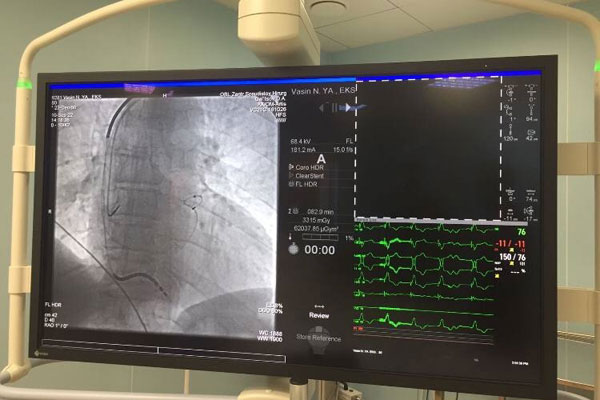

ОПТИМИЗИРУЙТЕ СВОИ КОРОНАРНЫЕ ИНТЕРВЕНЦИИ

В РЯЗГМУ ОБСУДИЛИ ВЕДЕНИЕ ПАЦИЕНТОВ С ТРОМБОЗОМ ВЕН

Здоровое сердце - 2023